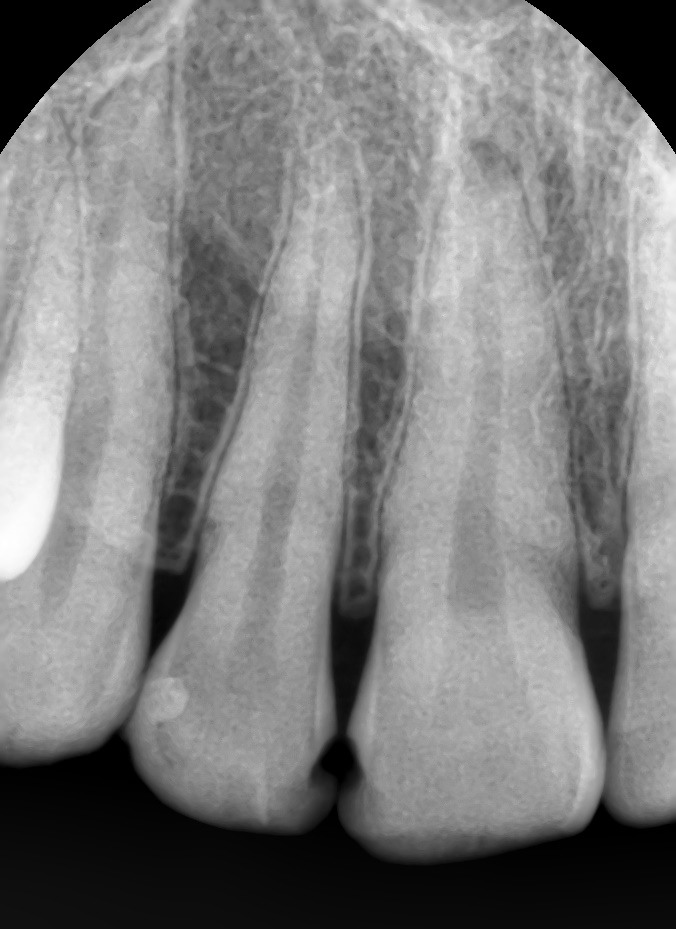

저희 치과에서 다시 레진치료를 받은 케이스입니다.

![[을지로/명동 근처 치과] 앞니 레진 치료사례 관련 이미지 1](https://pub-9f2bb3498faf4d1d8714b41df24753e3.r2.dev/content/clinics/archive/rseeanjxfu/naver_blog/yonseiyegam/assets/by_hash/7561b3582a51ea6e48260df4452b24066c04ddc5a5a8b077599ece32175d0466.jpg)

레진 떨어진 부위가 엑스레이상에도 확연히 보입니다.